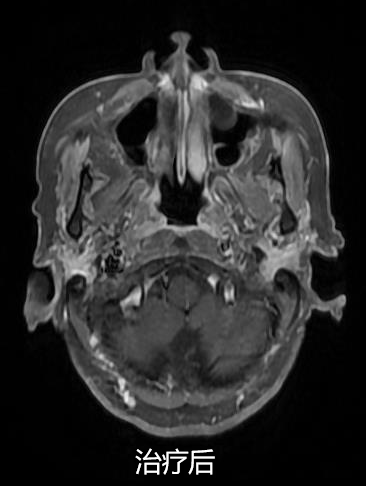

同步放化療(鼻咽癌伴頸部淋巴結轉移)